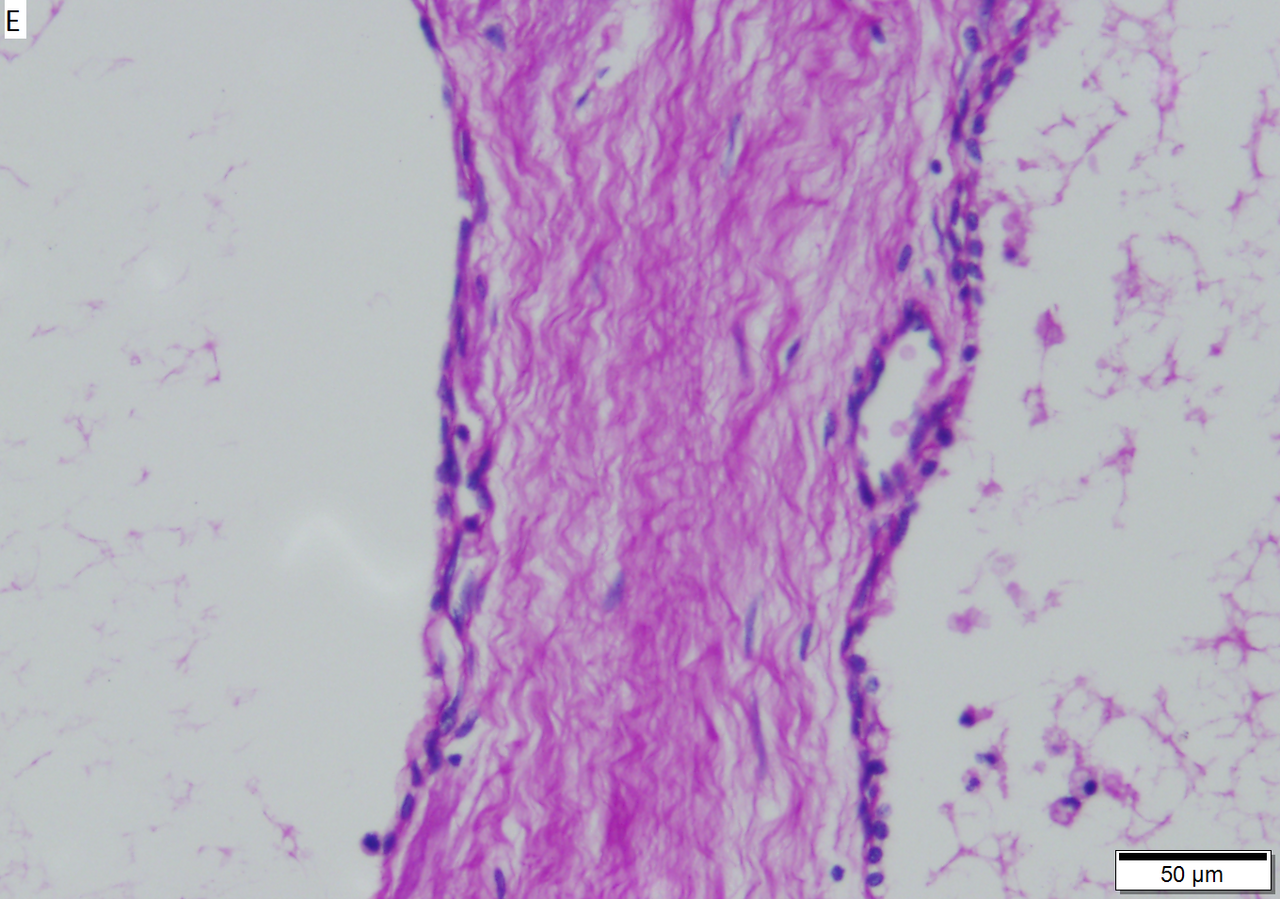

<br>Microcystic serous cystadenoma of pancreas in a 62 year old woman. A. The tumor showed a central scar with multiple minute cysts; slight pressure yielded clear fluid. B. The mass comprises microcysts numberless. C. Cysts bear single cell linings with bland, amitotic nuclei. D. PAS without diastase shows positive cytoplasmic material. E. PAS with diastase shows the cytoplasmic material has been digested away. F. Keratin shows positive staining lining cells. | |||

Microcystic serous cystadenoma of pancreas in a 62 year old woman. A. The tumor showed a central scar with multiple minute cysts; slight pressure yielded clear fluid. B. The mass comprises microcysts numberless. C. Cysts bear single cell linings with bland, amitotic nuclei. D. PAS without diastase shows positive cytoplasmic material. E. PAS with diastase shows the cytoplasmic material has been digested away. F. Keratin shows positive staining lining cells.